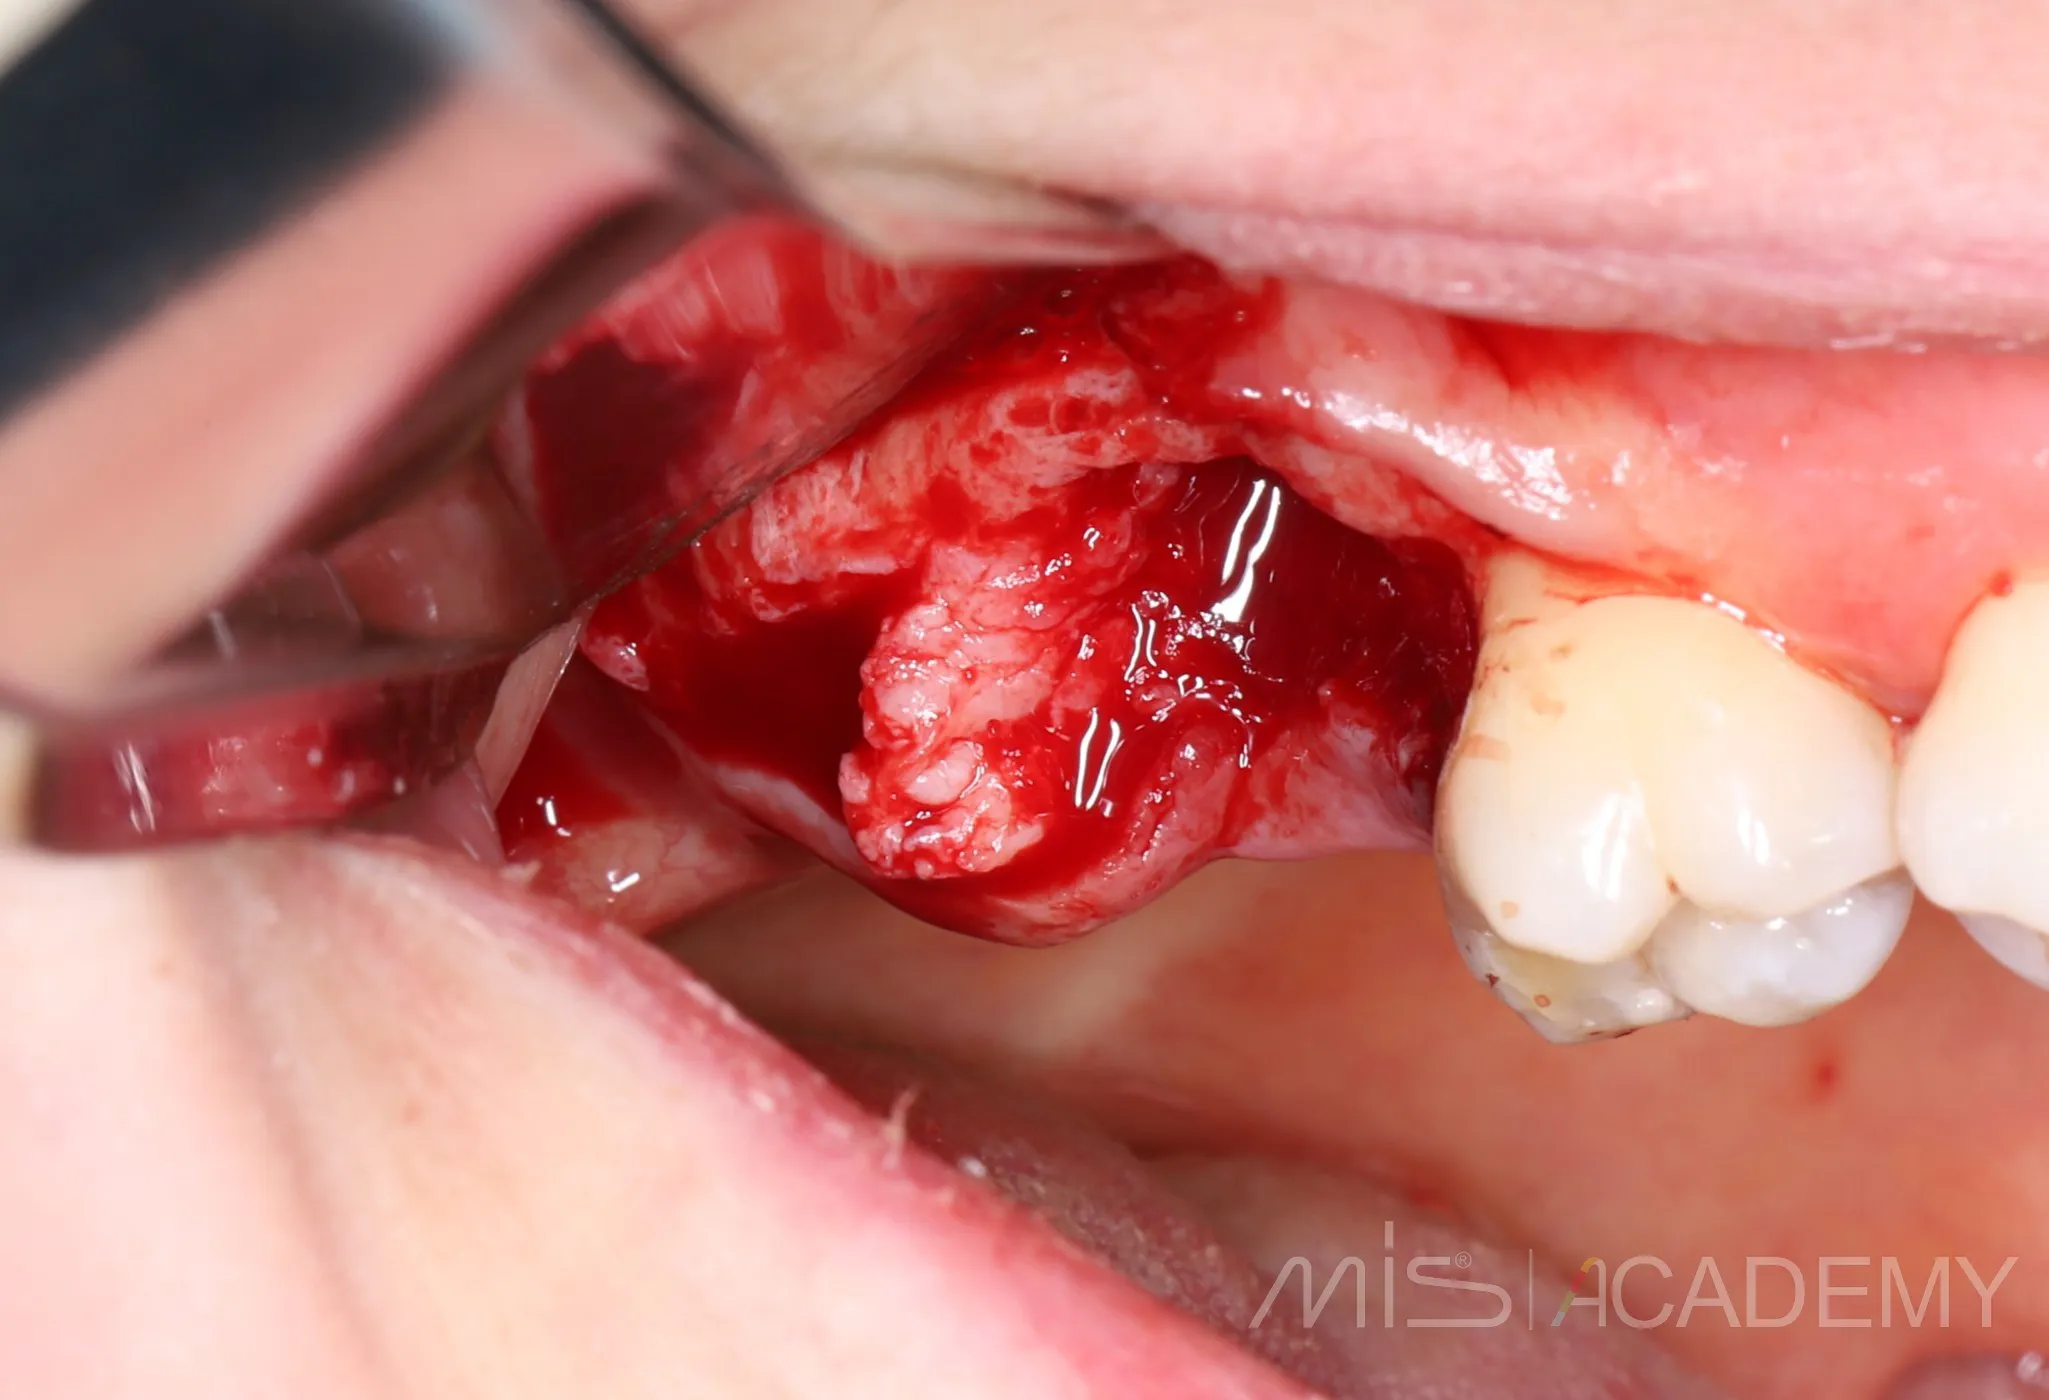

2 года назад закрыл соустье с пазухой в обл 17 зуба лоскутом с бугра «через себя»

Да, я подсмотрел это способ у Артура Политова. Сейчас пациентка пришла на плановый осмотр с другой проблемой,